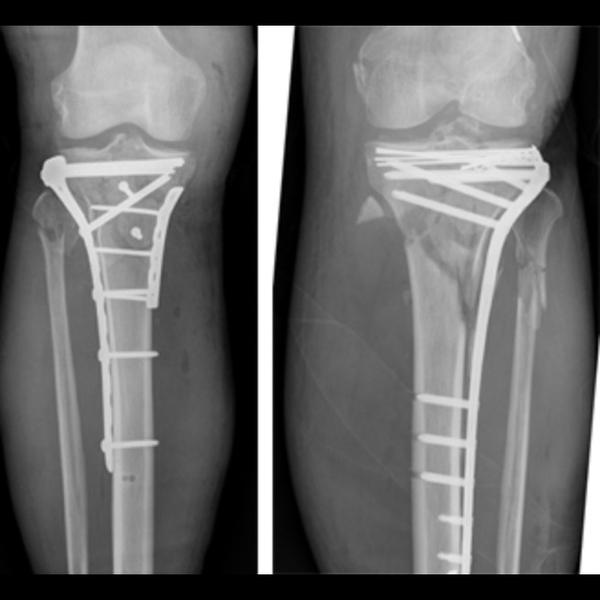

Best Tibia Plate Remove Surgery in Thane